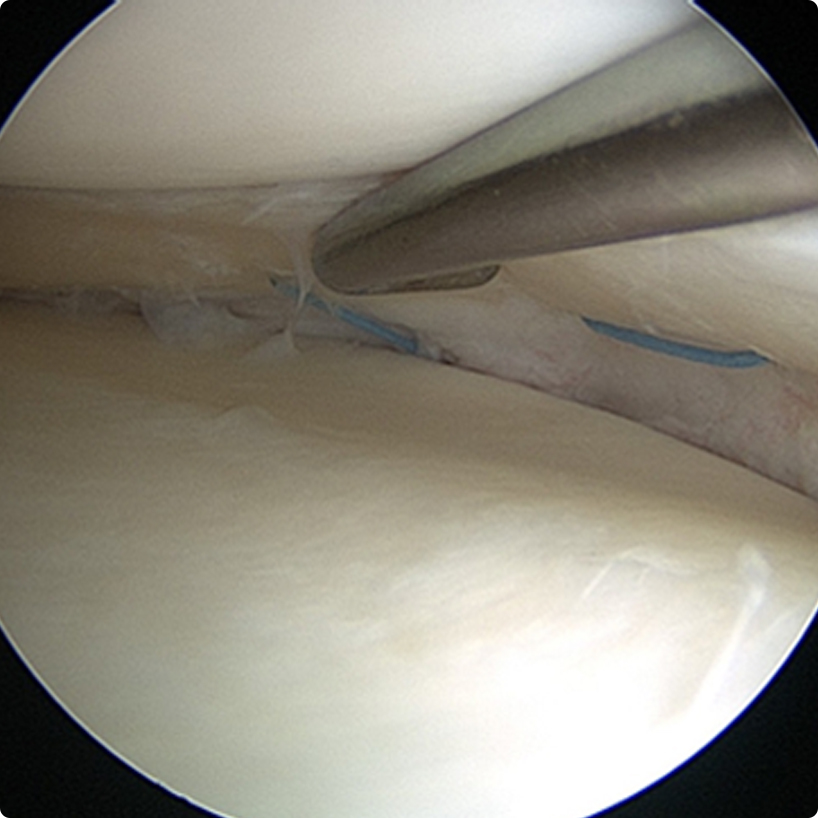

Tanı konulduktan sonra hastanın şikayetlerinin ciddiyeti, günlük hayatındaki işlevlerine etkisi göz önüne alınarak tedavisi yapılır. Genellikle acil olan durumlar (örneğin diz ekleminin kilitlenmesi, hareket ettirilememesi) dışında öncelikle ağrı kesici ve yangı giderici ilaçlar, istirahat, egzersiz, soğuk uygulama ve aktivitelerin düzenlenmesini içeren bir tedavi verilir. Bu tedavi ile başarı sağlanamadığında özellikle genç yaş grubundaki yırtıklarda cerrahi tedavi gerekir. Cerrahi tedavi günümüzde eklemin kamerayla görüntülenmesi eşliğinde yapılan “artroskopik-kapalı” yöntemlerle yapılır.

Bu yöntemle diz ekleminin içi görüntülenerek tanı doğrulanır, ek sorunlar varsa tespit edilir ve aynı anda tedavileri yapılabilir.

Amaç mümkün olduğunca fazla sağlam menisküs dokusu bırakarak yırtık kısmın çıkarılması, veya eğer yırtık kanlanan çevresel bölgedeyse dikişlerle tamir edilmesidir.